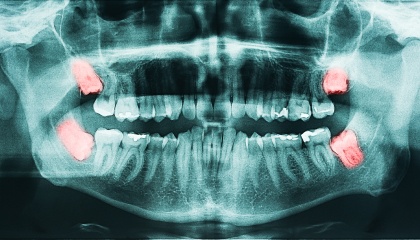

Wisdom Teeth Removal…

When it comes to removing wisdom teeth with IV sedation you don’t want a substitute for experience. We have been removing wisdom teeth for over a decade.

At Today Dental in Northlake, we’ve streamlined the wisdom teeth removal process to minimize post-operative pain and swelling. We use state-of-the-art technology and pharmaceutical medications for a straightforward outpatient appointment.

Removing wisdom teeth can vary depending on factors such as the number of teeth being extracted, their position (fully or partially in bone), and any potential complications. At Today Dental of Northlake an average, a straightforward extraction of four wisdom teeth usually takes about 30 minutes (not including pre and post op time). If teeth are impacted (embedded in the jawbone) or located horizontally, the procedure may take longer.

We'll review your medical history and discuss the procedure with you. X-rays will be taken to assess the position and condition of the wisdom teeth. We’ll provide a detailed treatment plan including costs, timing and go over any questions you might have. Before the extractions, we’ll administer local anesthesia and in most cases IV sedation to ensure a pain-free experience. Once you’re numb and/or sedated, the extractions will take place, involving the careful removal of the wisdom teeth. Post-extraction, gauze will be placed at the extraction site to control bleeding, and you'll receive instructions for post-operative care. The entire process typically takes about 60 to 90 minutes, including preparation and recovery time.

Do I need my wisdom teeth removed?